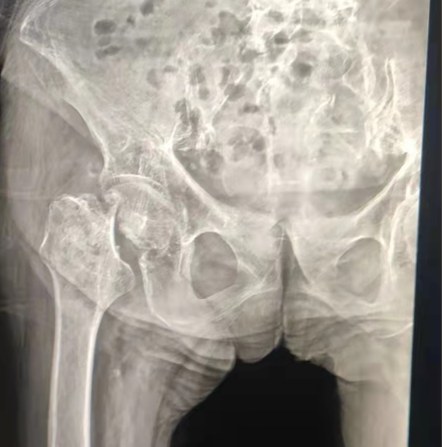

Case Sharing | A 70 years-old patient, received the total hip replacement with Lepu cemented hip system